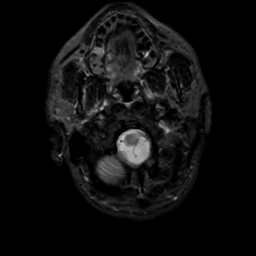

MR Study #5, March 10, 1991 -- Slice #4

[Home][Help][Clinical][Tour 1][Tour 2] Slice 4